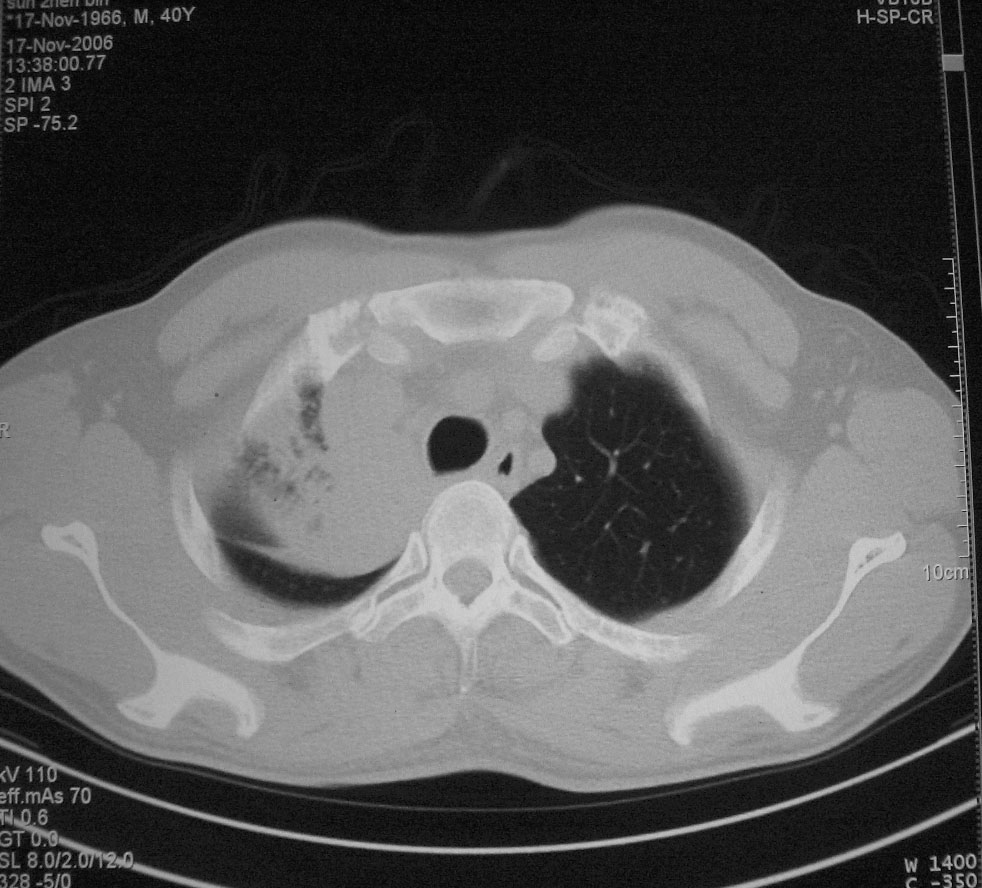

标题: CT5485:[原创]肺部占位请讨论

右肺上叶中央型肺癌并上叶肺不张、纵隔淋巴结肿大

右上叶支气管后壁明显增厚,支持右肺上叶中央型肺癌伴右上叶肺不张、纵隔淋巴结肿大。

右上叶支气管后壁明显增厚,支持右肺上叶中央型肺癌伴右上叶肺不张、纵隔淋巴结肿大。建议支气管镜检查。

右上叶支气管肺癌并右上叶阻塞性不张,右侧少量胸腔积液.

右上肺中央性肺癌伴右侧胸腔少量积液!右上肺胸膜下还有一小病灶,不完全排除结核,但个人支持恶性肿瘤!建议早穿刺活检。

右上叶支气管开口变窄,纵隔见肿大的淋巴结。支持右上叶中心型肺癌并右上叶不张纵隔淋巴结肿大。

右肺上叶中央型肺癌并上叶肺不张、纵隔淋巴结肿大.右侧少量胸腔积液。

右上肺中心型肺癌并肺不张,纵膈淋巴结肿大。右侧少量胸腔积液。

右肺上叶支气管后壁增厚,呈鼠尾状狭窄,纵隔内未见明显增大的淋巴结影,考虑为中央型肺癌伴右上肺不张

右肺上叶不张,考虑中央型肺癌。右侧胸膜肥厚

右肺上叶中央型肺癌并阻塞性炎症、阻塞性肺不张……

右上肺癌,肺不张,纵隔淋巴结肿大

右肺上叶中央型肺癌